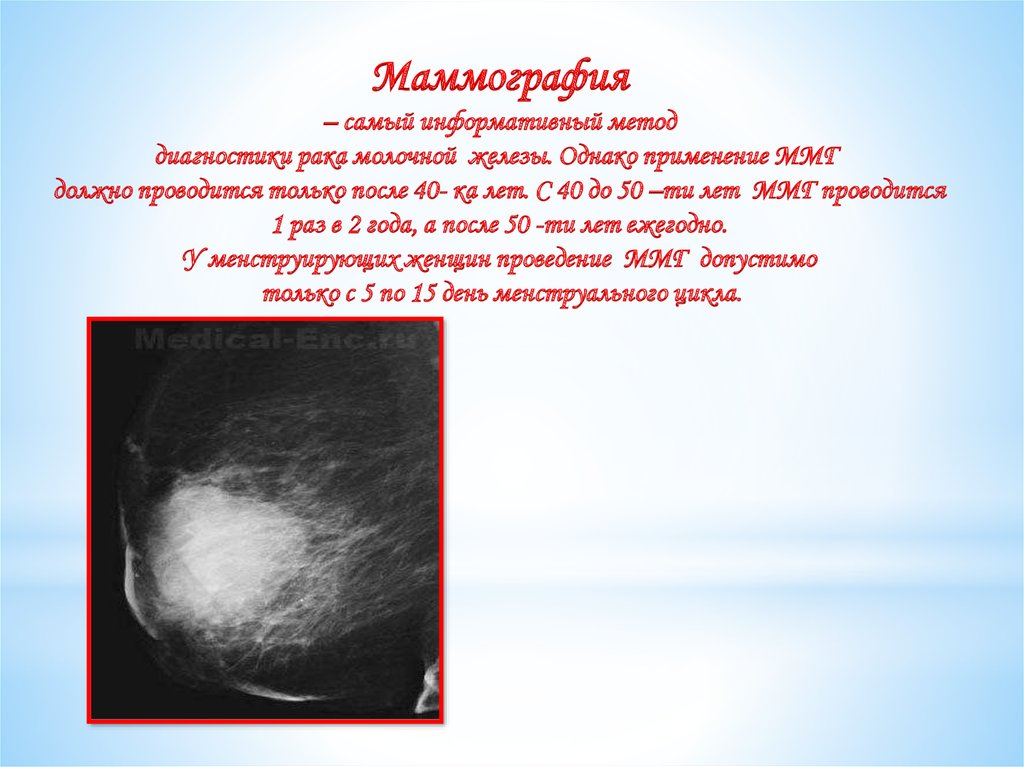

Гепатомегалия. Симптомы гепатомегалии. Умеренное увеличение печени. Умеренная гепатомегалия. Маммография косая проекция укладка. Маммография молочных желез. Маммография это исследование. Рентгеновская маммография.

Маммография косая проекция укладка. Маммография молочных желез. Маммография это исследование. Рентгеновская маммография. Подчелюстная слюнная железа на рентгене. Сиалография слюнных желез. Рентгенография слюнных желез. Контрастная сиалография слюнных желез.

Опухоль печени доброкачественная кт. Первичные злокачественные опухоли печени. Злокачественные новообразования печени кт. Первичные и Метастатические опухоли печени. Маммография. Маммограмма молочных желез. Маммография после 40 лет проводится.

Маммография. Маммограмма молочных желез. Маммография после 40 лет проводится. Виды роста злокачественных опухолей. Рост злокачественных новообразований. Злокачественные опухоли характеризуются. Форма злокачественной опухоли.